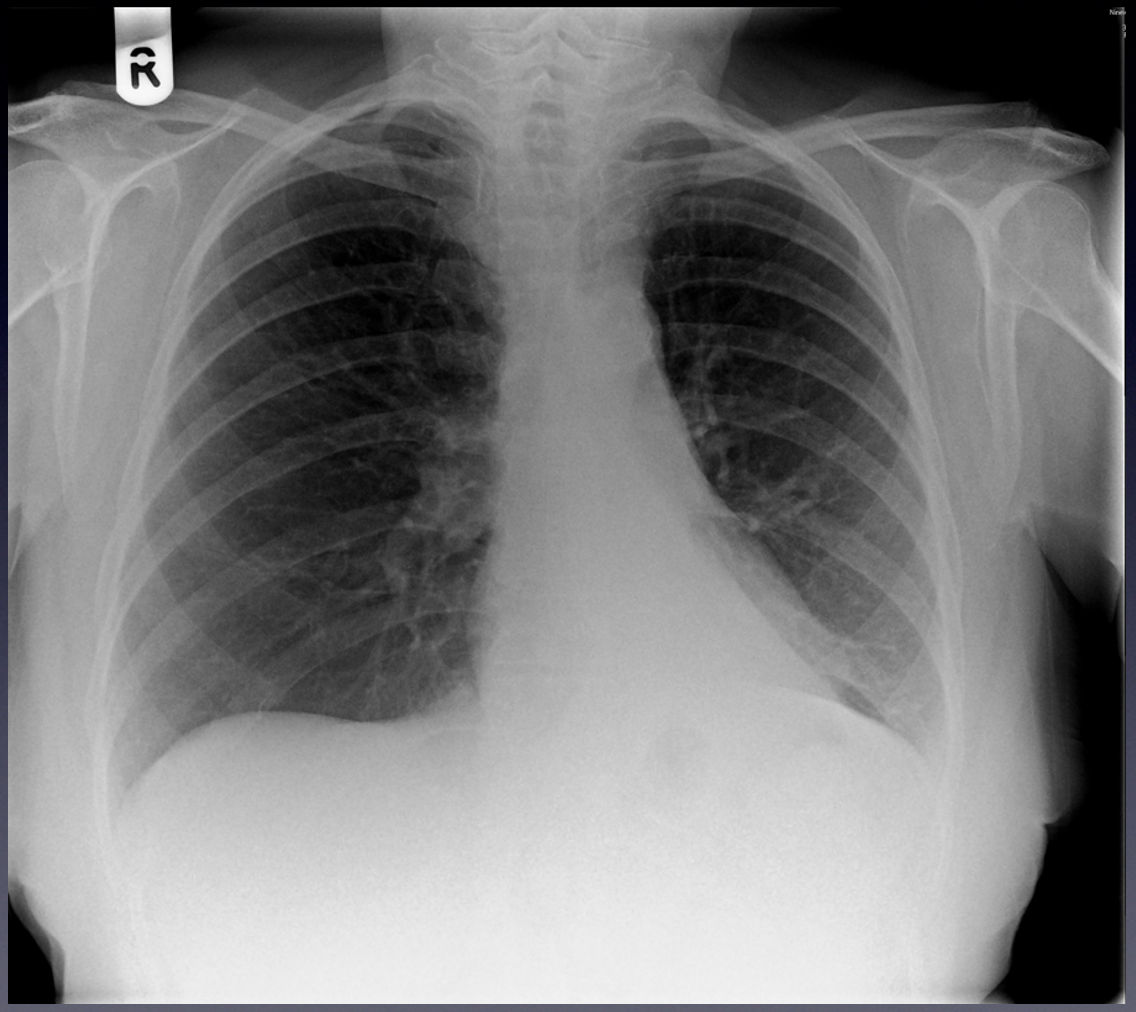

Normal CXR